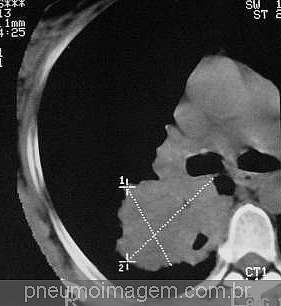

Clique aqui para ver imagens de câncer de pulmão não pequenas células no PneumoImagem.